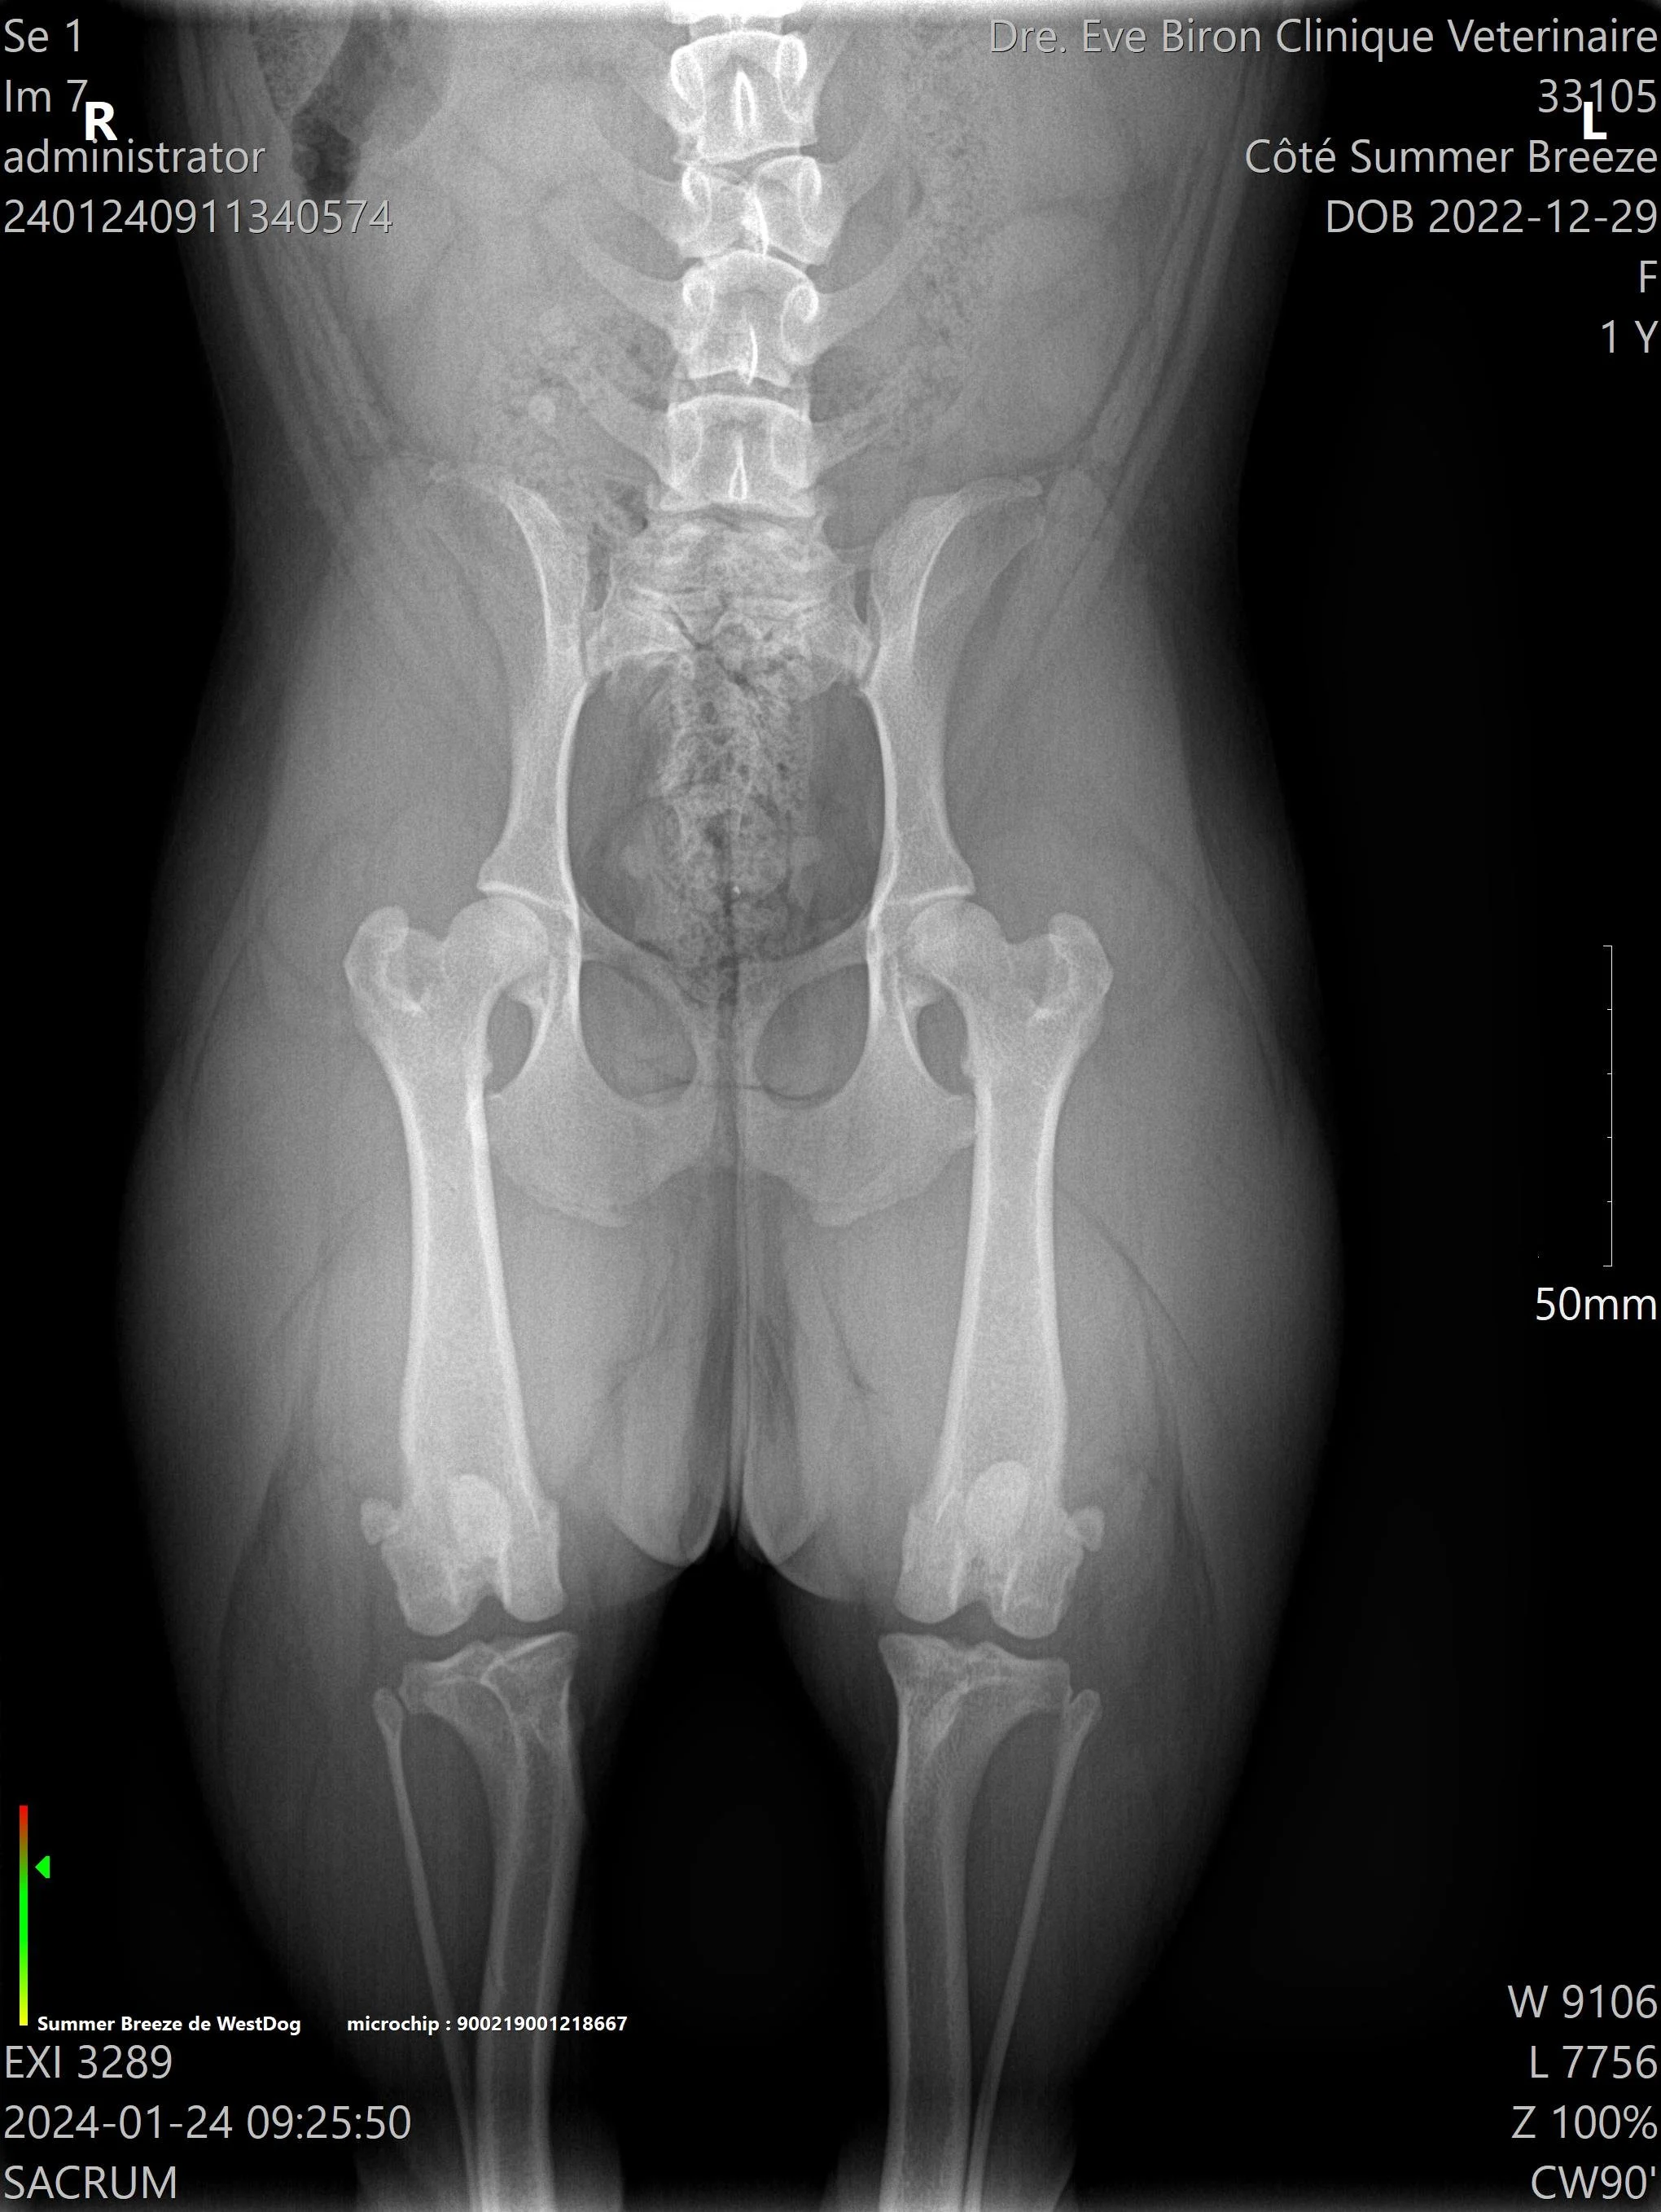

L’OFA recommande de faire des tests de biomécanique du chien: Dysplasie de la hanche, Luxation des rotules, Examen oculaire, évaluation cardiaque, Coude, Thyroïdite, et Trachée.

Tous ces tests doivent être fait par des vétérinaires et certains laboratoires accrédités. La vérification de l’enregistrement original du chien AKC et de l’identification par micropuce ou tatou est obligatoire pour que le vétérinaire puisse signer et envoyer les radiographies de façon électronique, de la clinique vétérinaire à L’OFA et ainsi éviter les fraudes.

L'OFA est un organisme à but non lucratif situé aux États-Unis qui permet de publier les résultats des tests fait par les vétérinaires et les laboratoires accrédités. 3 vétérinaires indépendants spécialisés, évaluent les radiographies et leurs donnent des “quotes”. C’est une excellente façon de prouver qu’un éleveur a le souci de dépister des problèmes potentiels sur les animaux qu’il prévoit reproduire, et de montrer au public les résultats des épreuves complétées. Comme la majorité des gens ne sont pas spécialisés en lecture de radiographies, les notes données par L’OFA sont impartiales et permettent d’avoir une vraie vue d’ensemble.

Pour la méthode traditionnelle, celle de l’OFA (Orthopedic Foundation for Animals), une seule radiographie est prise. Avec la méthode PennHIP, ce sont trois prises de vues qui sont réalisées. Elles permettent au vétérinaire de détecter la présence d’arthrose dans l’articulation et de calculer le degré de relâchement (s’il y en a un). Le PennHIP peut être effectué à partir de l’âge de 16 semaines, ce qui en fait une méthode de dépistage précoce. La dysplasie de la hanche est une maladie génétique qui affecte les chiots dès leur plus jeune âge.